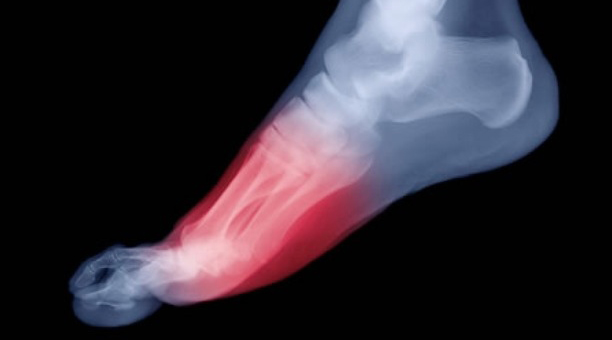

La metatarsalgia es una inflamación en la zona anterior plantar del pie, justo la zona de la almohadilla plantar, cerca de los dedos del pie. Se manifiesta como un dolor agudo que se acentúa al caminar, estar varias horas de pie o en una misma posición.

La metatarsalgia puede ser de origen nervioso (Neuroma de Morton) o de origen mecánico. Éstas últimas son las más comunes, que se originan por la propia forma incorrecta de caminar.

En la parte anterior del pie hay cinco huesos largos llamados metatarsianos. Son los responsables de soportar todo el peso de nuestro cuerpo y son el último punto de contacto con el suelo cuando realizamos el despegue del pie al caminar. Por eso, reciben mucha presión durante todo el ciclo de la marcha.

Este aumento de presión constante y repetitiva en la zona metatarsal produce dolor e inflamación. Esta sensación, que empeora al caminar, puede ir acompañada de durezas o callos en las zonas de máxima presión. Además, el pie cavo y el uso prolongado de tacones aumentan el riesgo de desarrollar esta patología.